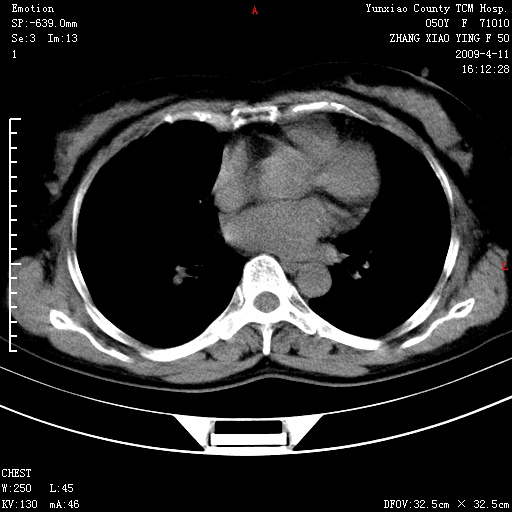

标题: CT19324:胸闷1周伴咳嗽 [打印本页]

标题: CT19324:胸闷1周伴咳嗽

病灶周围肺纹受压移位走行较柔和,余肺里实质均匀,纹理如常,肺间质无显著纤维化,支持考虑孤立性肺囊肿

考虑右肺中叶肺囊肿。